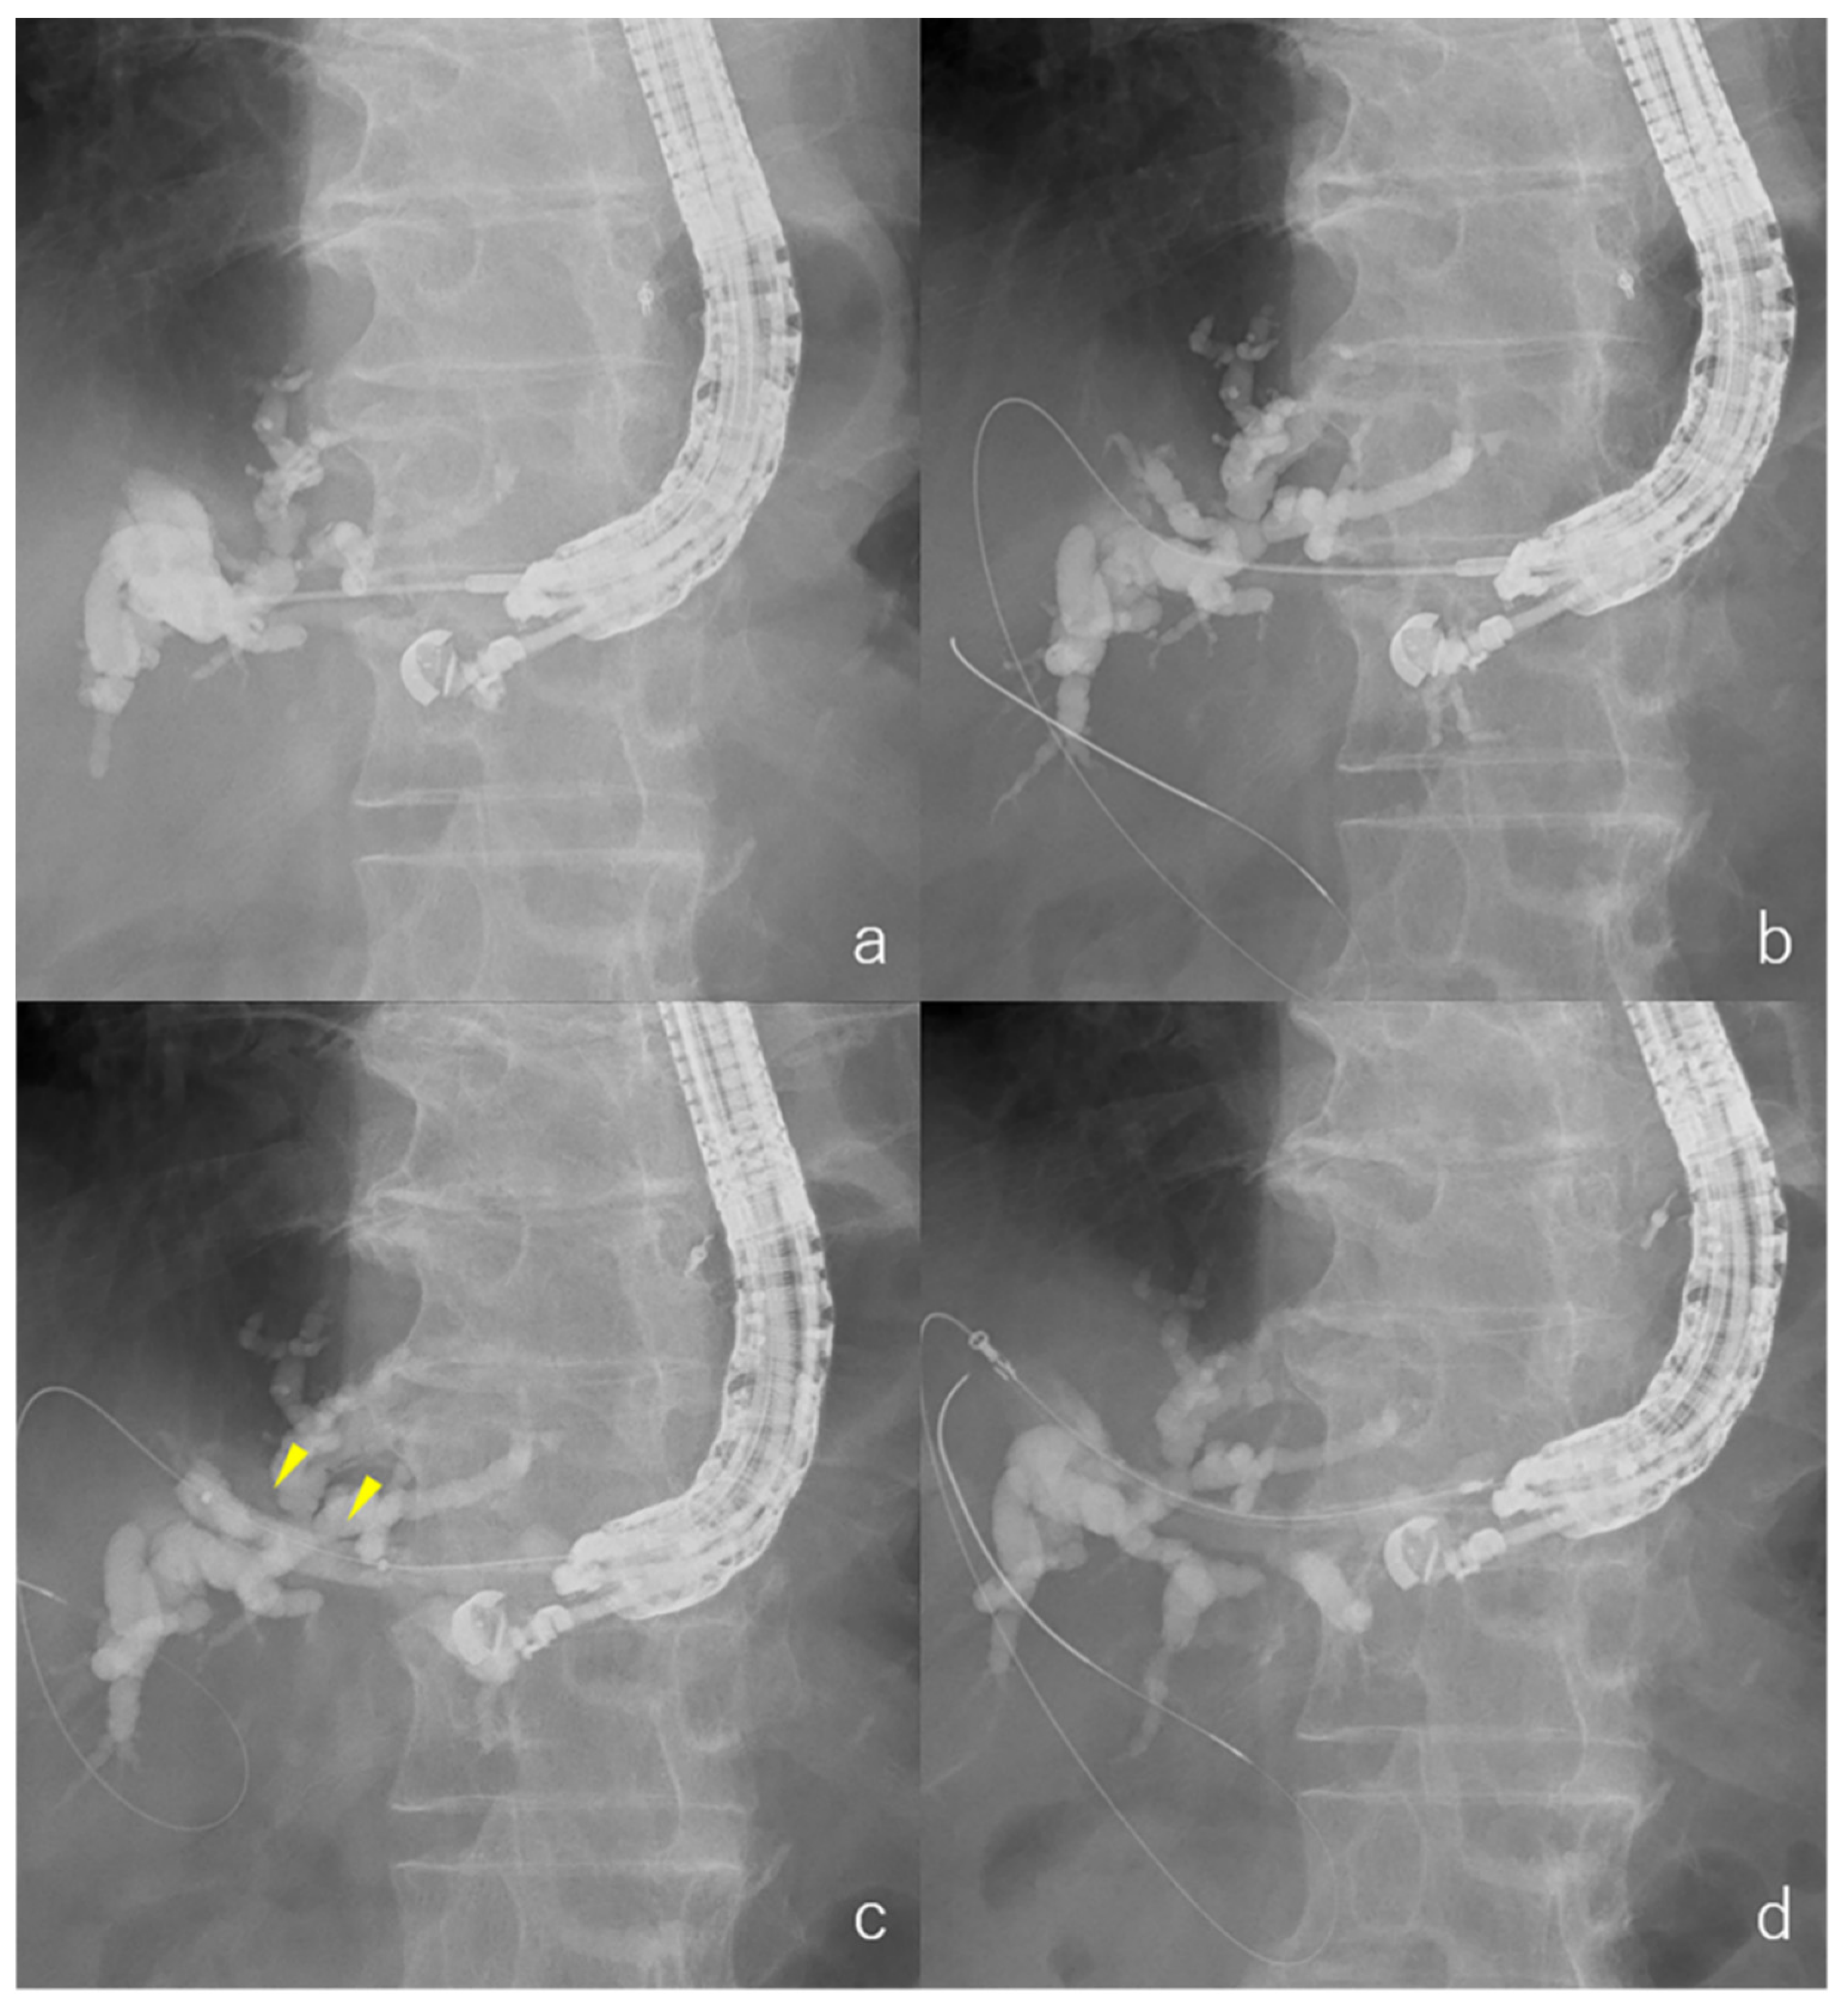

2.3. EUS-HGS Procedures